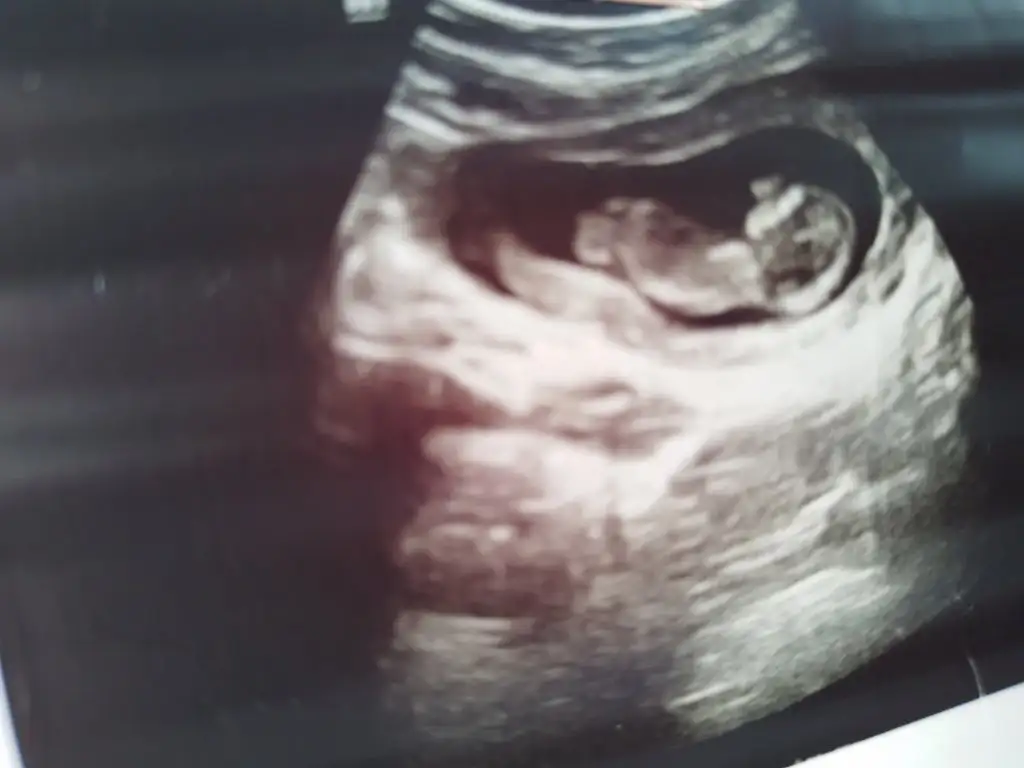

Benimkine de bakabilir misiniz doktorum 11+5te kız dedi 13+6da erkek dedi

İlk 3 fotoğraf 13+6

Son 2 fotoğraf 11+5